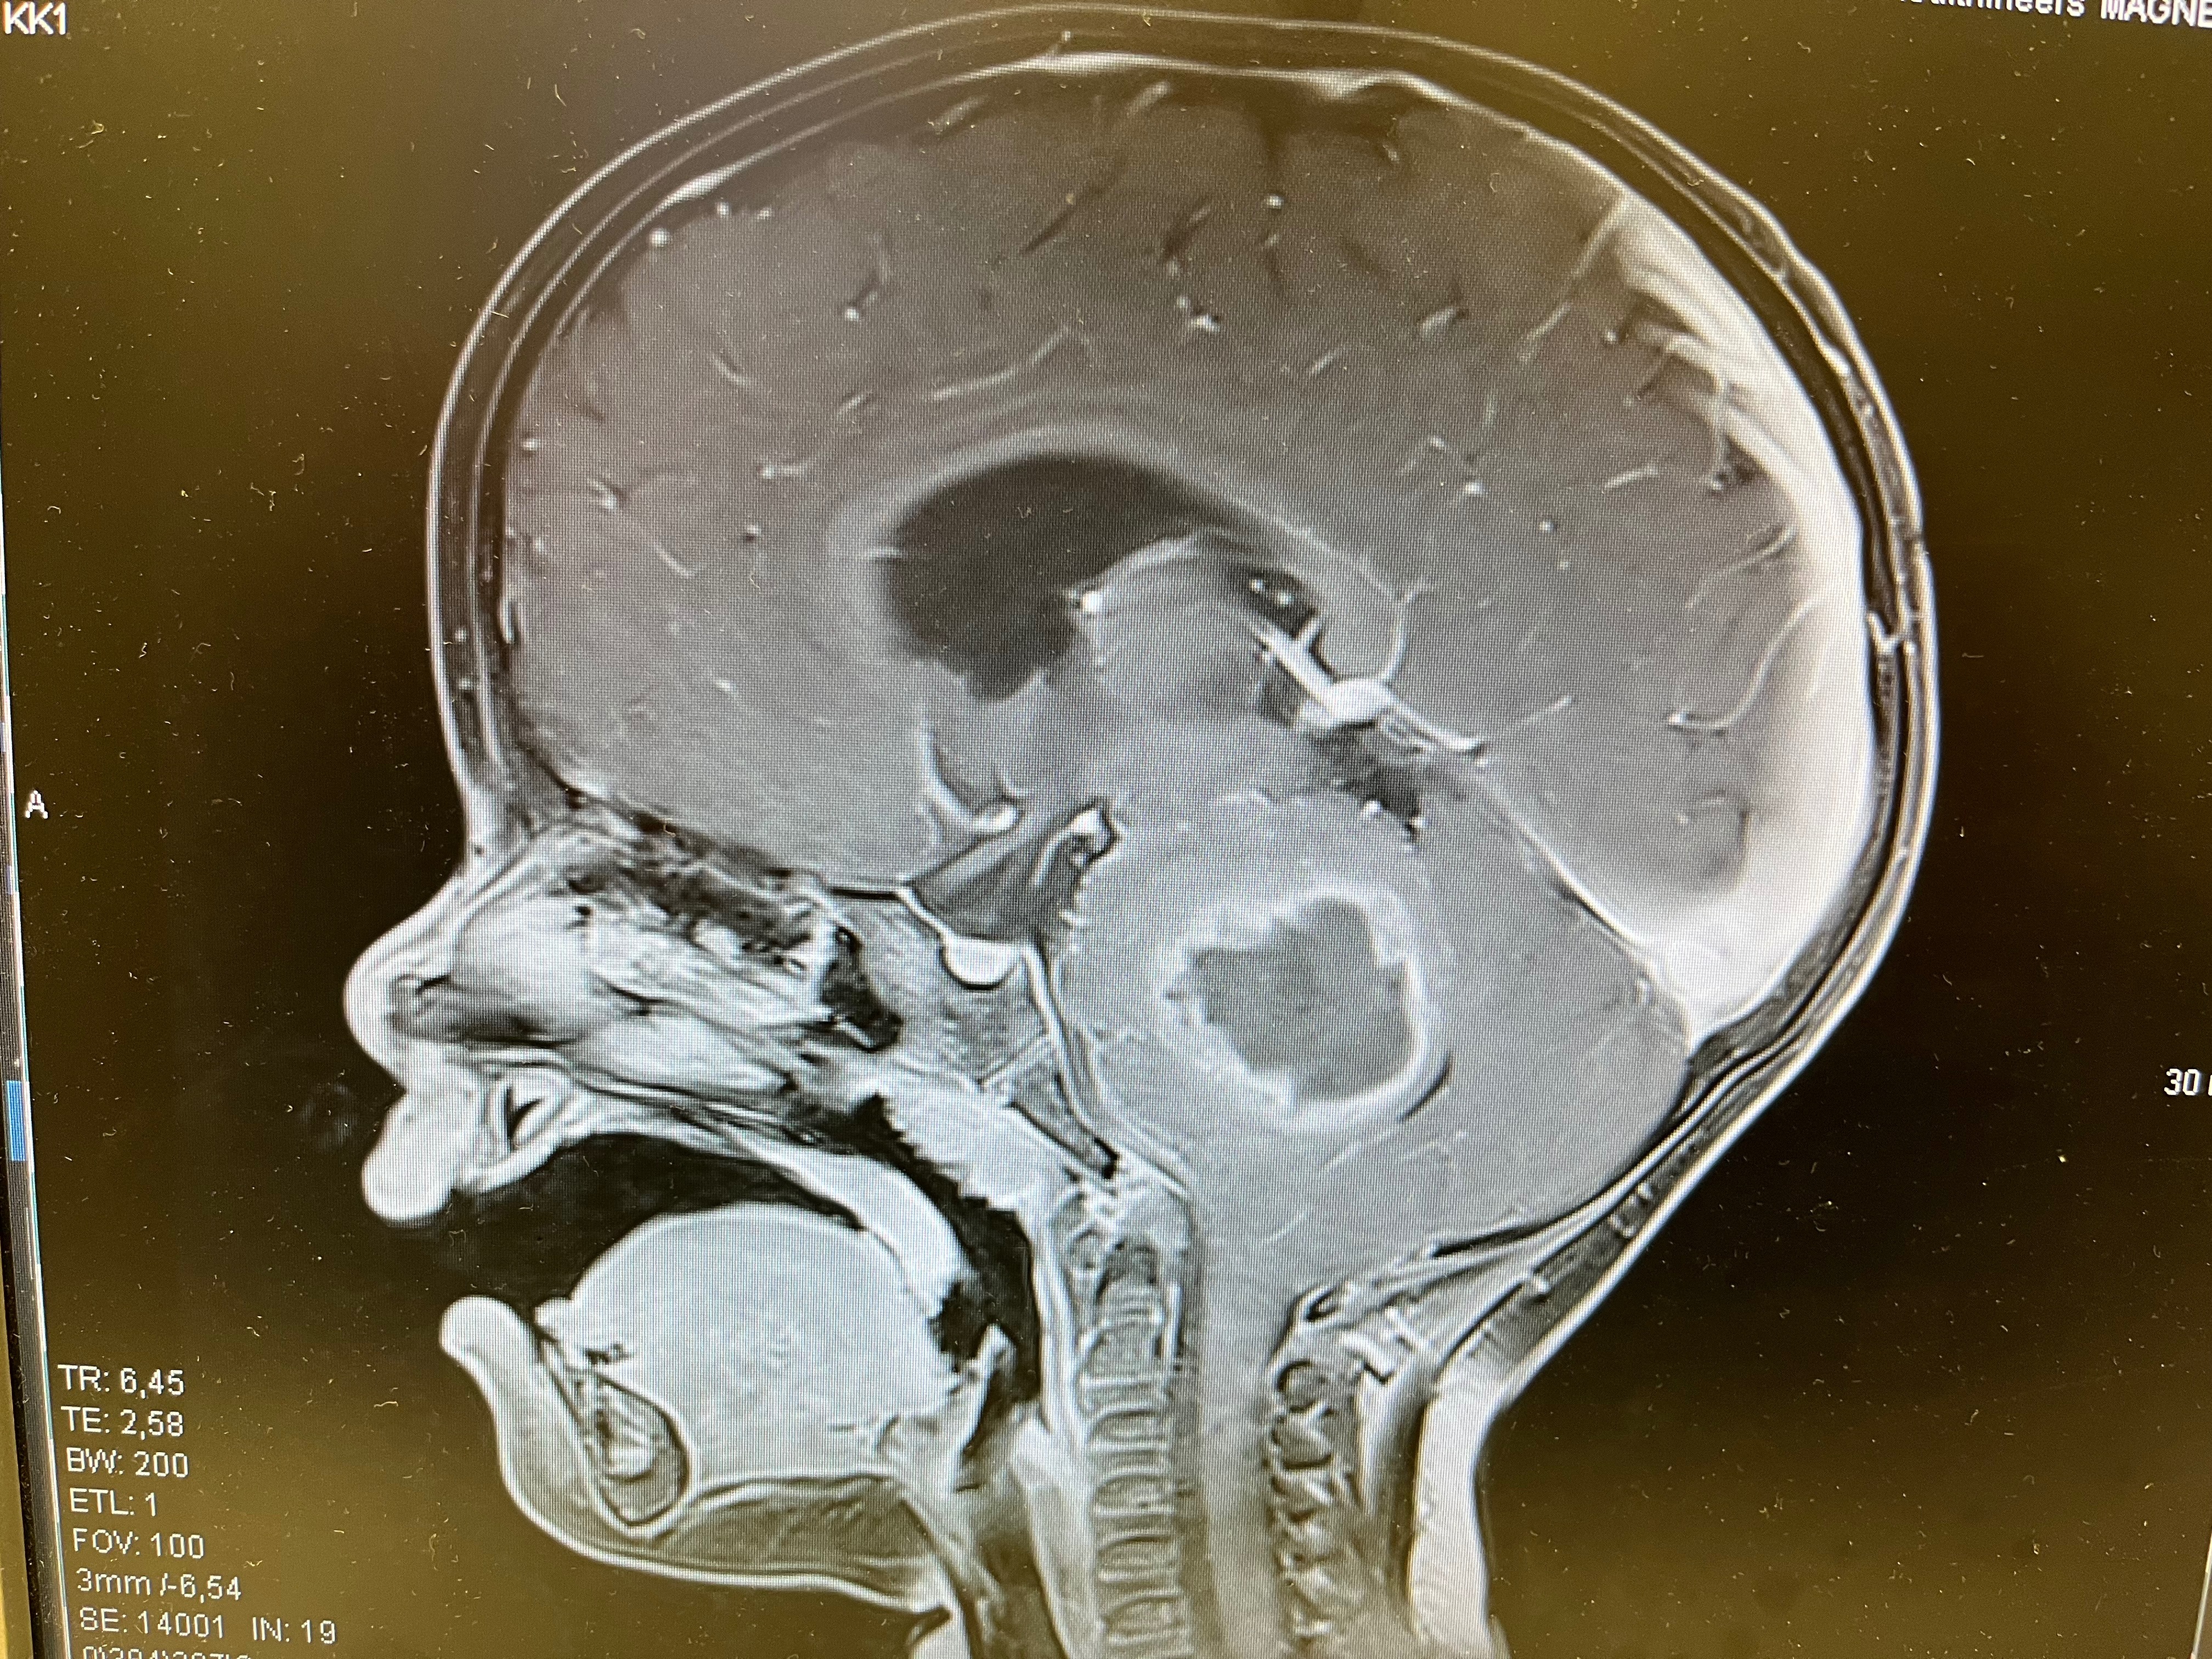

Bei Marlene wurde ein Ponsgliom diagnostiziert. DIPG (diffuses intrinsisches Ponsgliom) ist ein seltener sehr aggressiver Hirntumor, welcher im Hirnstamm wächst. Die Lebenserwartung liegt bei 9-12 Monaten nach Diagnosestellung. Nur 10% der Betroffenen leben länger als 2 Jahre.

Sie kämpfte sich zurück in IHR Leben. Im Juni 2025 zeigte ein Kontroll-MRT, dass die Bestrahlung gewirkt hatte. Der Tumor ist minimal kleiner geworden. Dennoch ist dieses Ponsgliom eine tickende Zeitbombe.